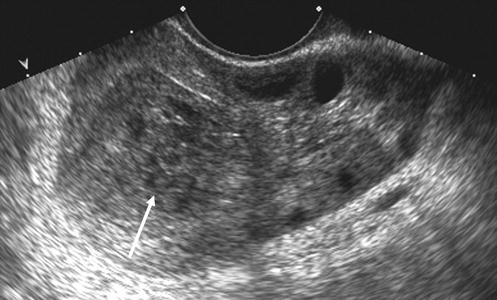

A TVS , also known as an internal scan , is most commonly done to confirm that you are pregnant . It's more accurate and gives clearer images than an abdominal ultrasound in early pregnancy . A transvaginal scan can: Detect the presence of the sac and/or an embryo . Find out if you're carrying more than one baby as early as the fifth week of your pregnancy .

While scanning with TVS in the normal pregnancy, fetal pole/fetus was seen in 43 cases (93 .5%), whereas in comparison with TAS FP/fetus was seen in 33 cases (71 .7%) . In the abnormal pregnancy, FP/fetus was seen in 11 cases with TVS , as compared to six cases with TAS .

The earlier in pregnancy a scan is performed, the more accurate the age assignment from crown-rump length . The initial age assignment should not be revised on subsequent scans 5 . Overall, the accuracy of sonographic dating in the first trimester is ~5 days (95% confidence range) .